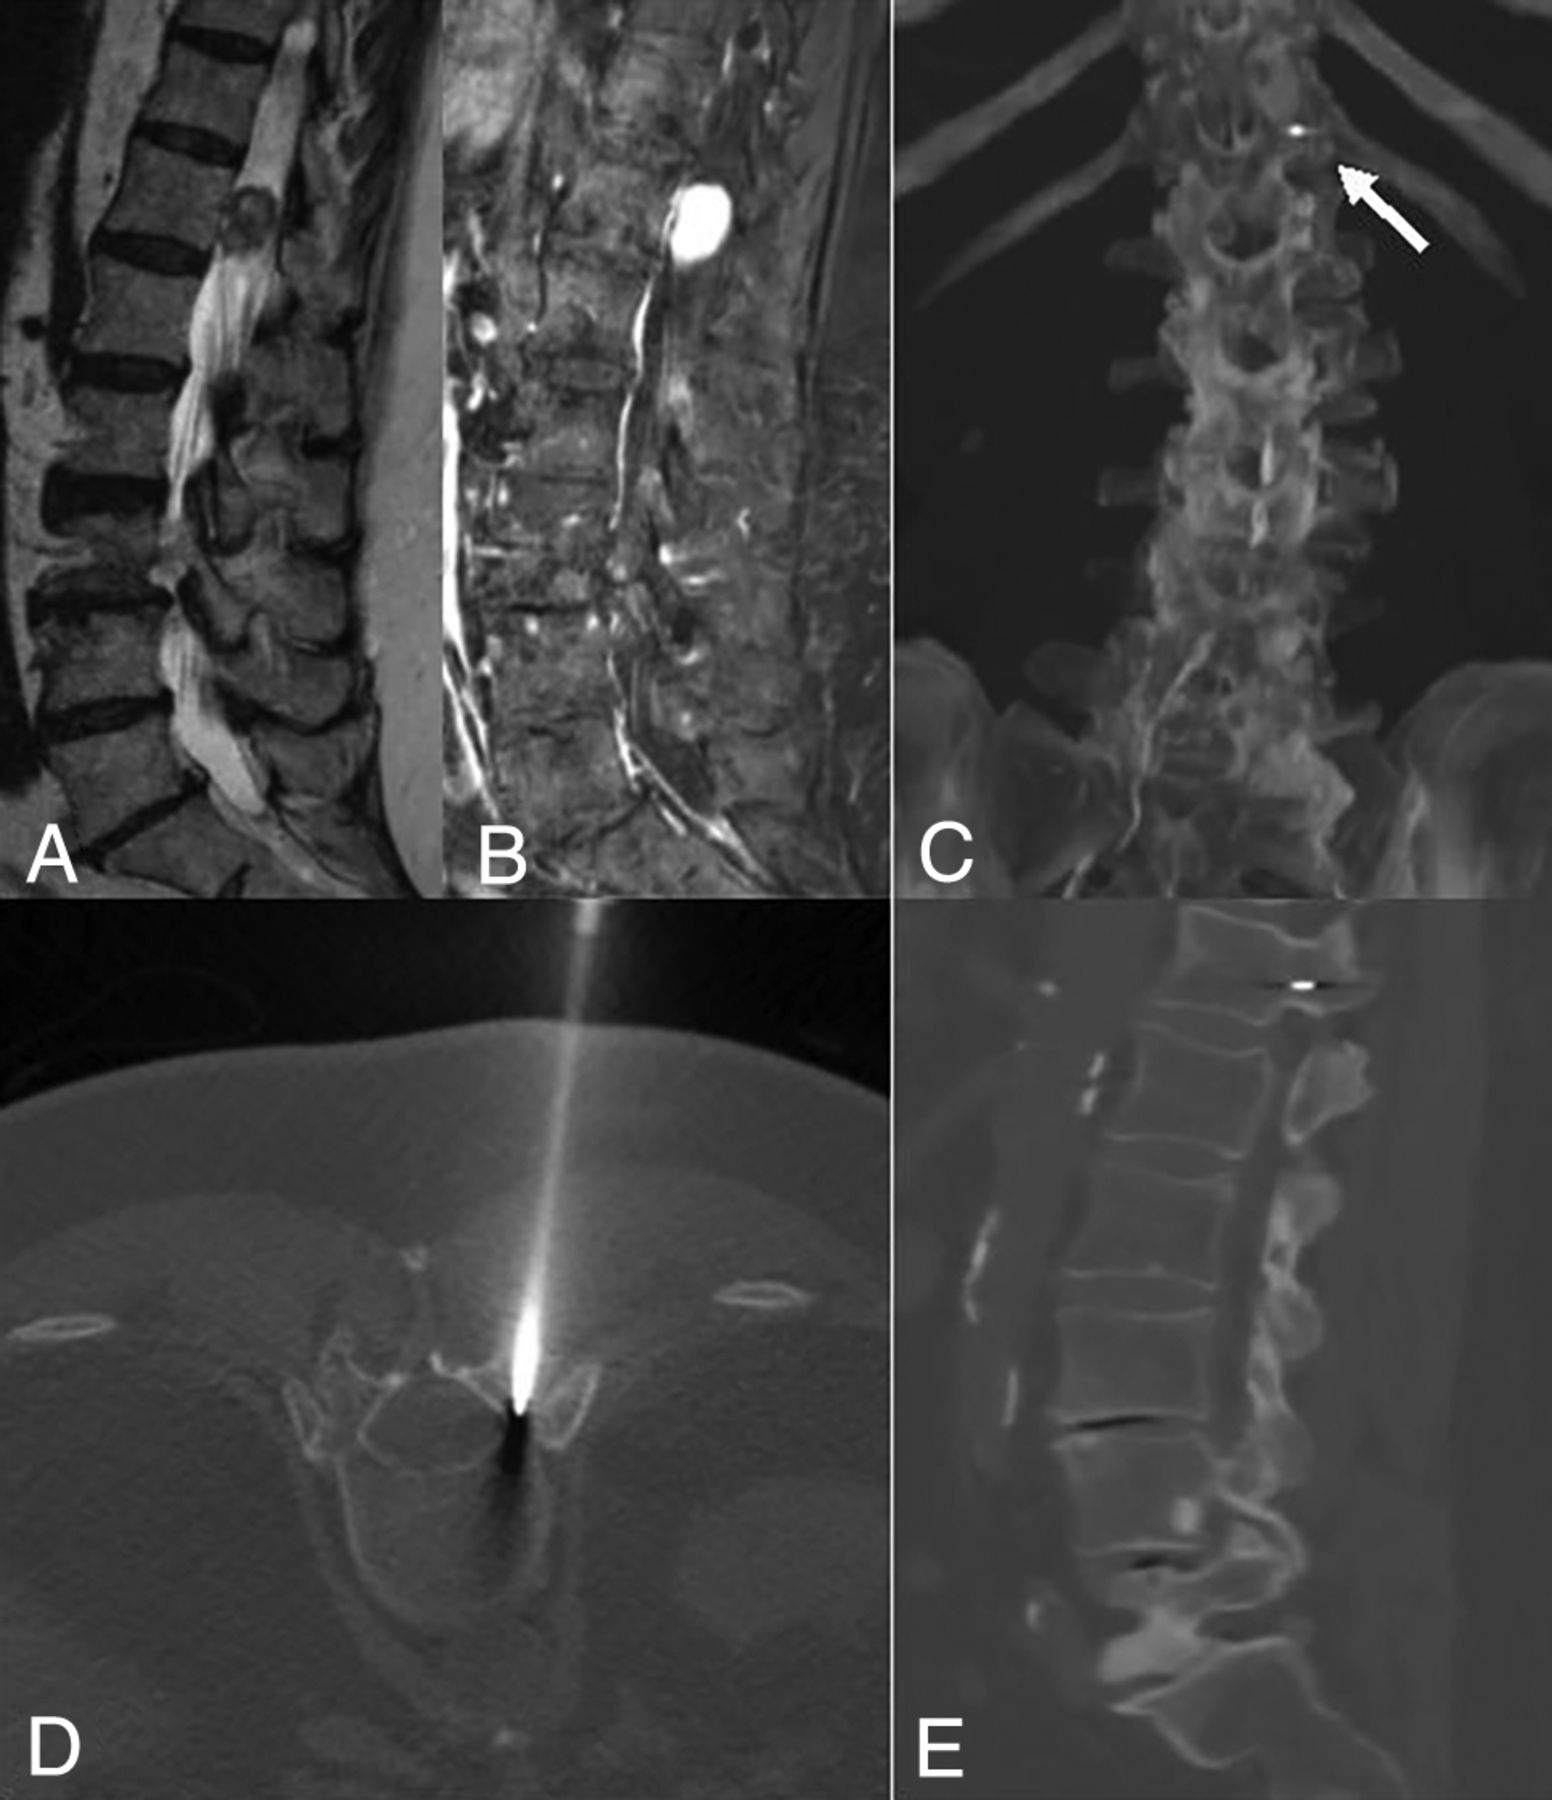

CT-guided gold fiducial marker placement. A and B, Sagittal T2WI and fat-saturated postcontrast T1WI demonstrate an intradural extramedullary, lobulated, homogeneously intensely enhancing mass that was resected and found to be a schwannoma on pathology. D, Intraprocedural axial CT bone windows at T12 demonstrate a coaxial bone access needle located within the left pedicle of T12. C and E, Postprocedural CT MIP and sagittal reconstructions confirm the gold fiducial marker placement in the left T12 pedicle. Arrow points toward gold fiducial marker.